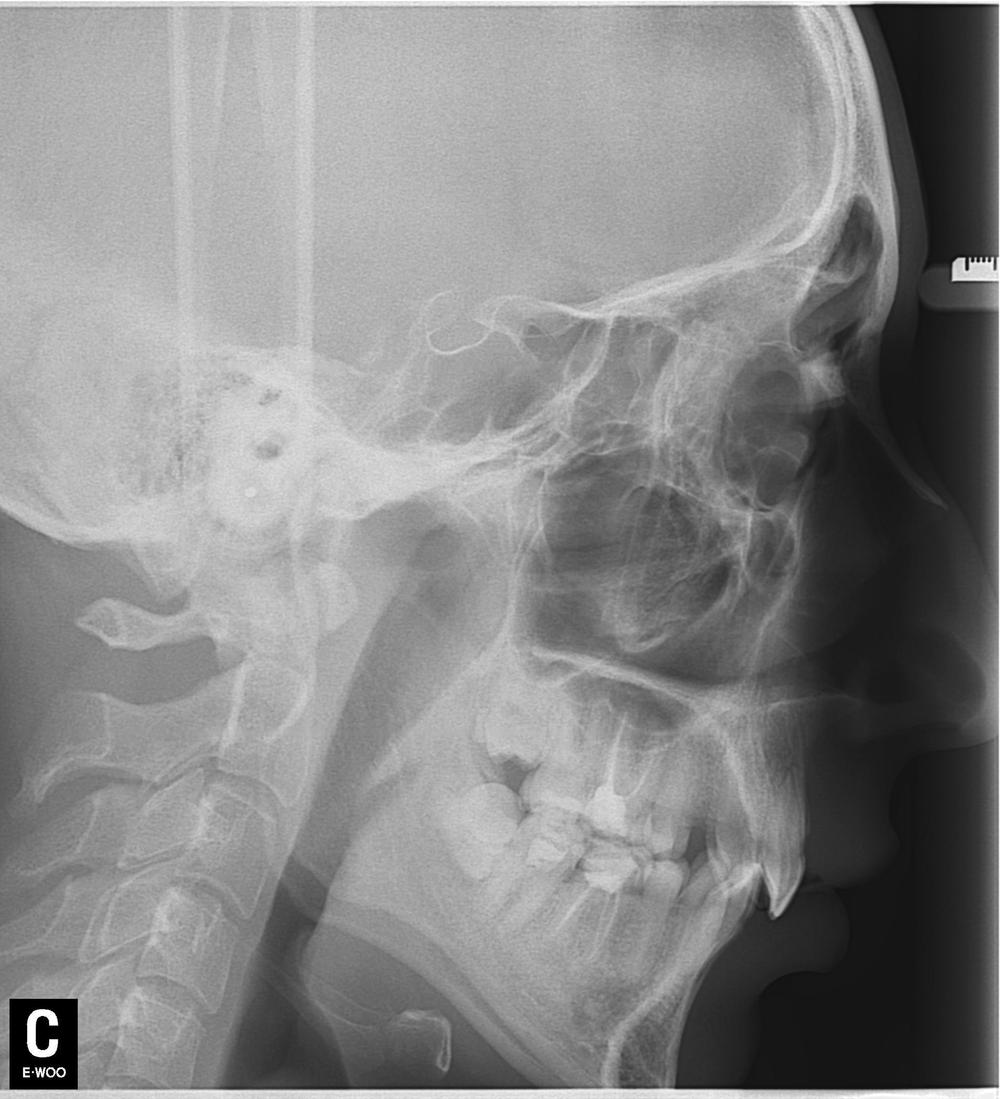

Но мы отвлеклись. Вот снимок пациентки после лечения.

Кроме зубов "мудрости" не удалено ничего. Тут проведено лечение корневых каналов, вкладки, коронки. Какие удаленные 22 зуба? Это бред СМИ, нацеленный на непонятную травлю. Конечно, кого заинтересует новость "пациентке не понравился результат лечения и она подала в суд", фу, уныло. А вот "шок!!врачи-убийцы рядом!! Схватили, выдрали 22 здоровых зуба!!и вкатали счет на миллион!!не допустим врачебного произвола!!!111" - вот это уже вызывает подрыв у очень многих.